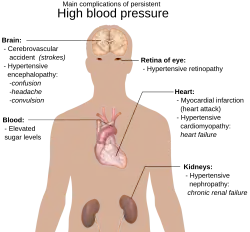

Кардиология изучает такие патологические состояния, как ишемическая болезнь сердца (ИБС), гипертоническая болезнь, врождённые пороки сердца, приобретённые пороки сердца, цереброваскулярные заболевания и другие. Сегодня доля кардиологической патологии в структуре смертности населения развитых стран составляет 40—60 %, при этом продолжающийся рост заболеваемости и поражение людей всё более молодого возраста, что делает сердечно-сосудистые заболевания важнейшей медико-социальной проблемой здравоохранения.

- гипертоническая болезнь;